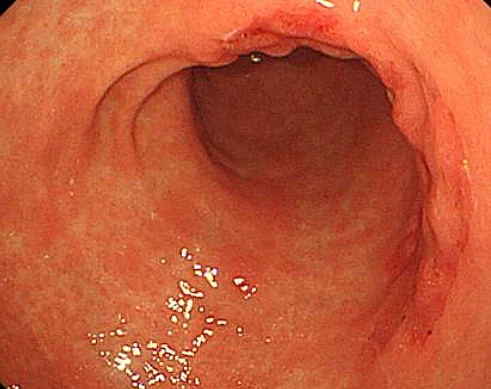

근래 3년 안에 내시경 받아보신 분들 많으시죠. 그럼 꼭 돈을 챙겨 받으셔야 합니다. 내시경 후 받을 수 있는 돈! 그것은 바로 보'험금입니다 위내시경과 대장내시경 받았을 때 청구가 가능한 경우가 총 4종류가 있습니다. 실비, 생명보'험에 등록한 사람들이라면 오늘 내용 꼭 검토하시고 반드시 지급금 받아가시길 권합니다.

본래 건강검진 자체는 실비 보'험금 청구가 안되지만 건강검진을 통해 대장 내시경을 했어도 지급금을 받을 수 있습니다. 대장 내시경 중에 바로 용종을 제거했을 때입니다.즉 용종제거비, 조직검사비용은 보장 받을 수 있습니다. 약관에 따르면 검진 결과 이상의견이 있어 건강검진센 등에서 발생한 추가의료경비는 지급금 보증된다고 나와 있습니다.

그렇지만 보'험지급금을 청구하기 전 진단서에 용종을 제거했다는 내용이 확실해야 합니다. 진단서에 용종제거에 대한 내용이 잘 기재되어 있는지 꼭 검토 하시길 바랍니다.

대장 내시경 후 보'험금 받는 경우 두번째는 의사의 권유로 내시경을 받을 때입니다. 본디 건강검진 자체는 실비지급금 청구가 안되지만 의사가 직접 권유 했을 경우 실비 지급금을 받을 수 있습니다. 즉 내가 자발적으로 건강검진에서 내시경을 한것은 지급금 청구 대상이 안 되지만 의사가 권해서 받은 위내시경, 대장내시경은 실비 지급금 청구가 가능성합니다. 그러한 이유 때문에 치료 후 내시경 받고 보'험금 놓친 사람들은 약관 한번 검토 하시고 지급 청구하기를 권합니다.

그런데 만약 의사 권유로 대장내시경을 받았고 용종까지 제거했다면 두가지 다 지급 받을 수 있을까요? 용종 제거 비용은 당연히 받고 대장 내시경 검진 비용까지도 모두 보장받을 수 있다고 하니 꼭 잊지말고 챙겨 받으시길 바랍니다.

내시경 후 지급금 받는 경우 세번째는 바로 수술비 특약에 등록했을 때입니다. 보증약관에 따르면 수술은 인체에 절단 등 생체특정부위를 잘라내는 것을 의미합니다. 몸에 있는 용종을 제거했기 때문에 보증약관에서 말하는 수술의 일종이라고 합니다. 그렇지만 수술비 특약이라고 해서 전부 보증이 되는 건 아닙니다.

생명보'험사의 종수술비 특약이나 손해보'험사의 질병 수술비 특약에 가입되어 입는 경우 특약에 등록 가격과 종류에 따라 10만원에서50만원까지 차등지급받을 수 있습니다. 예를들면 내가 가입한 생명보'험 증권 특약에 1종 수술, 2종 수술, 3종 수술 이런식으로 나와 있다면 보증이 가능합니다. 당연히 가입된 상품의 약관에 따라 지급금에는 차가 있으니 세부적인 내용은 보'험사에 꼭 문의해보시기 바랍니다.

참고로 지급금은 용종 갯수에 상관없이 한 번만 지급이 됩니다. 즉 용종을 5개 제거하거나 10개를 제거하더라도 보'험금은 딱 한번만 지급된다고 합니다. 그렇다면 1년에 한번씩 용종제거를 하는 경우는 어떻게 될까요? 매해 한번씩지급금이 나온다고 하니 꼭 매년 챙겨 받으시길 바랍니다.

그런데 지금 "나 여태까지 대장 내시경하고 용종제거 했지만 지급금 한 푼도 못 받았는데?" 이렇게 억울 하신 사람들 많으실겁니다. 용종 제거 후 3년이 지나지 않았다면 보'험금청구 가능하다고 하니 지금 바로 검토하셔서 지급청구 해보시기 바랍니다.

내시경 후 지급금 받는 네번째는 제자리암으로 판명 났을 때입니다. 대장 내시경 검진를 하고 용종을 떼어내고 조직검사를 시행했더니 제자리암인 경우라면 유사암 진단금을 받을 수 있습니다. 제자리암이란 0기에 관련하는 극초기에 암으로, 종양이 장기 제일 바깥쪽 부분인 점박에 나타났지만 점막 하층까진 도달하지 못한 상황를 의미합니다. 하지만 문제는 제자리암의 경우 지급금을 쉽게 지급 해주려고 하지 않기 때문에 손해사정사와 같은 전문가를 통해 도움을 받아보시는게 좋은 방법입니다.